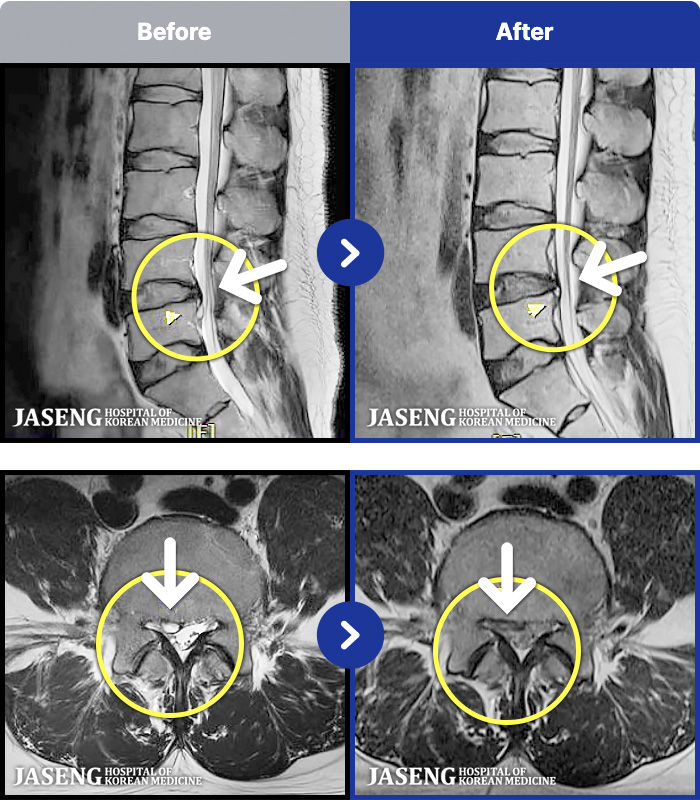

- MRI ġ

MRI ġ

1,240 MRI ũ ʸ Ȯϼ.